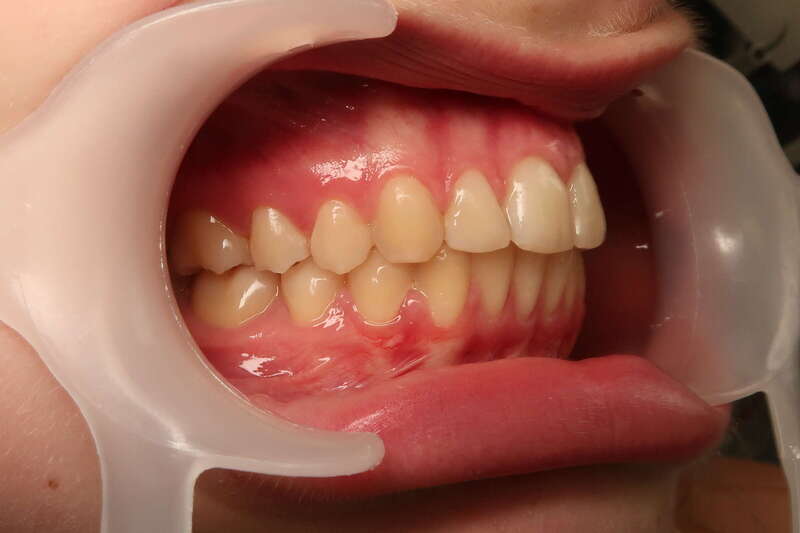

Ce cas d’interception chez un enfant de 8 ans démontre l'efficacité des aligneurs pour corriger des troubles fonctionnels précoces. Le diagnostic présentait des inversions d'articulé provoquant une déviation de la mandibule vers la gauche et un décalage des milieux.

Grâce à une coopération exemplaire et un traitement totalement indolore, l'expansion de l'arcade a permis de recentrer la mâchoire. Cette intervention a littéralement remis la croissance sur les rails, neutralisant le risque d'asymétrie faciale squelettique.

• Correction fonctionnelle : Recentrage immédiat de la mandibule et des milieux inter-incisifs.

• Prévention : Création d'un environnement favorable pour les dents définitives à venir.

• Bien-être : Approche douce respectant le confort de l'enfant.

C'est une étape fondamentale qui simplifie l'avenir orthodontique du patient tout en garantissant un développement facial harmonieux.

Avant